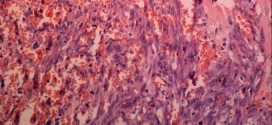

El tumor esplénico maligno. Tumor maligno en general y especialmente el formado por células epiteliales, a saber. Los canceres se dividen en dos grandes categorías de carcinoma y sarcoma u otros. La característica básica de la malignidad es una anormalidad de las células, transmitida a las células hijas, que se manifiesta por la reducción del control del crecimiento y la …

Los tumores mucinosos están caracterizados por quistes y glándulas revestidas por células que contienen moco. Representan un 15% de los tumores ováricos. Aproximadamente un 75% son benignos, un 10% borderline; y un 15%, carcinomas. Los tumores de ovario mucinoso, representan el 15% de los tumores epiteliales de ovario, pudiendo corresponder a la estirpe serosa, mucinosa, endometrioide, células claras o células …